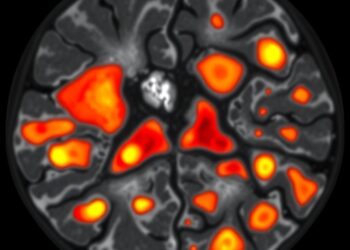

Spatial Analysis Reveals Immune-Rich Regions in Diffuse Large B-Cell Lymphoma Tumors, Highlighting New Treatment Opportunities

In a groundbreaking study published in Nature Genetics, researchers at The University of Texas MD Anderson Cancer Center have unveiled ...